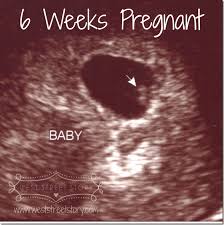

Transvaginal ultrasound by contrast can detect pregnancies earlier at approximately 4 to 5 weeks gestation. Prompt diagnosis made possible by transvaginal ultrasound can therefore result in earlier treatment. Monochorionic twins are detected by heart beat after 6 full weeks have passed. For women who conceive naturally having an ultrasound at five weeks seems pretty early since many don t even know they re pregnant yet.

But for women and couples who have undergone fertility treatments the five week ultrasound is an important insight to understanding if your pregnancy is established and on its way to developing successfully. This is usually at four to five weeks after a pregnant woman s last period. What to expect during a 5 week ultrasound if you re 5 weeks pregnant your ultrasound will be done via the vagina as opposed to transabdominal ultrasounds that are typically performed later on in. Generally you aren t able to see a heartbeat on an ultrasound until 6 weeks.

To detect any abnormalities. If you get a vaginal scan at 5 weeks the sonographer should be able to able to detect two separate gestational sacs if you re expecting dichorionic twins. That s when you re 6 0 weeks pregnant. To confirm whether the baby is growing normally.

Often you can see a heartbeat after 5 weeks although sometimes you ll have to wait a little longer. To show your placenta and baby s positioning. For non identical twins there are two gestational sacs and two yolk sacs with an embryo forming in each. Why should i have ultrasound at 5 weeks pregnancy.